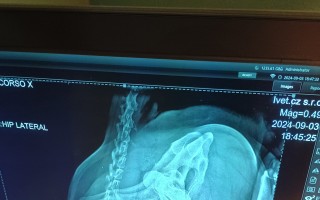

Rentgen po operaci:

Kačenka se stabilizovanou nožkou do vhodné polohy

rádi bychom vám dali vědět, že Kačenka včera podstoupila 3,5hodinovou operaci kyčle, na kterou jste přišpěli 😊. Pan doktor použil metodu tzv. kotvy, což znamená, že provrtal několik tunýlků, které spojil skrz kyčelní kloub a pánevní jamku do správné pozice.

Nyní má Kačenka 70–80% šanci, že kyčel bude úplně v pořádku. V opačném případě by muselo dojít k tzv. resekci kyčle, ale doufáme, že to nebude nutné.